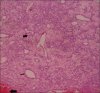

Nasal lobular capillary hemangioma is a rare benign tumor of the paranasal sinuses. This lesion is believed to grow rapidly in size over time. The exact etiopathogenesis is still a dilemma. We discuss a case of nasal lobular capillary hemangioma presenting with a history of epistaxis. Contrast enhanced computed tomography of paranasal sinuses revealed an intensely enhancing soft-tissue mass in the left nasal cavity and left middle and inferior meati with no obvious bony remodeling or destruction. We present imaging and pathologic features of nasal lobular capillary hemangioma and differentiate it from other entities like nasal angiofibroma.